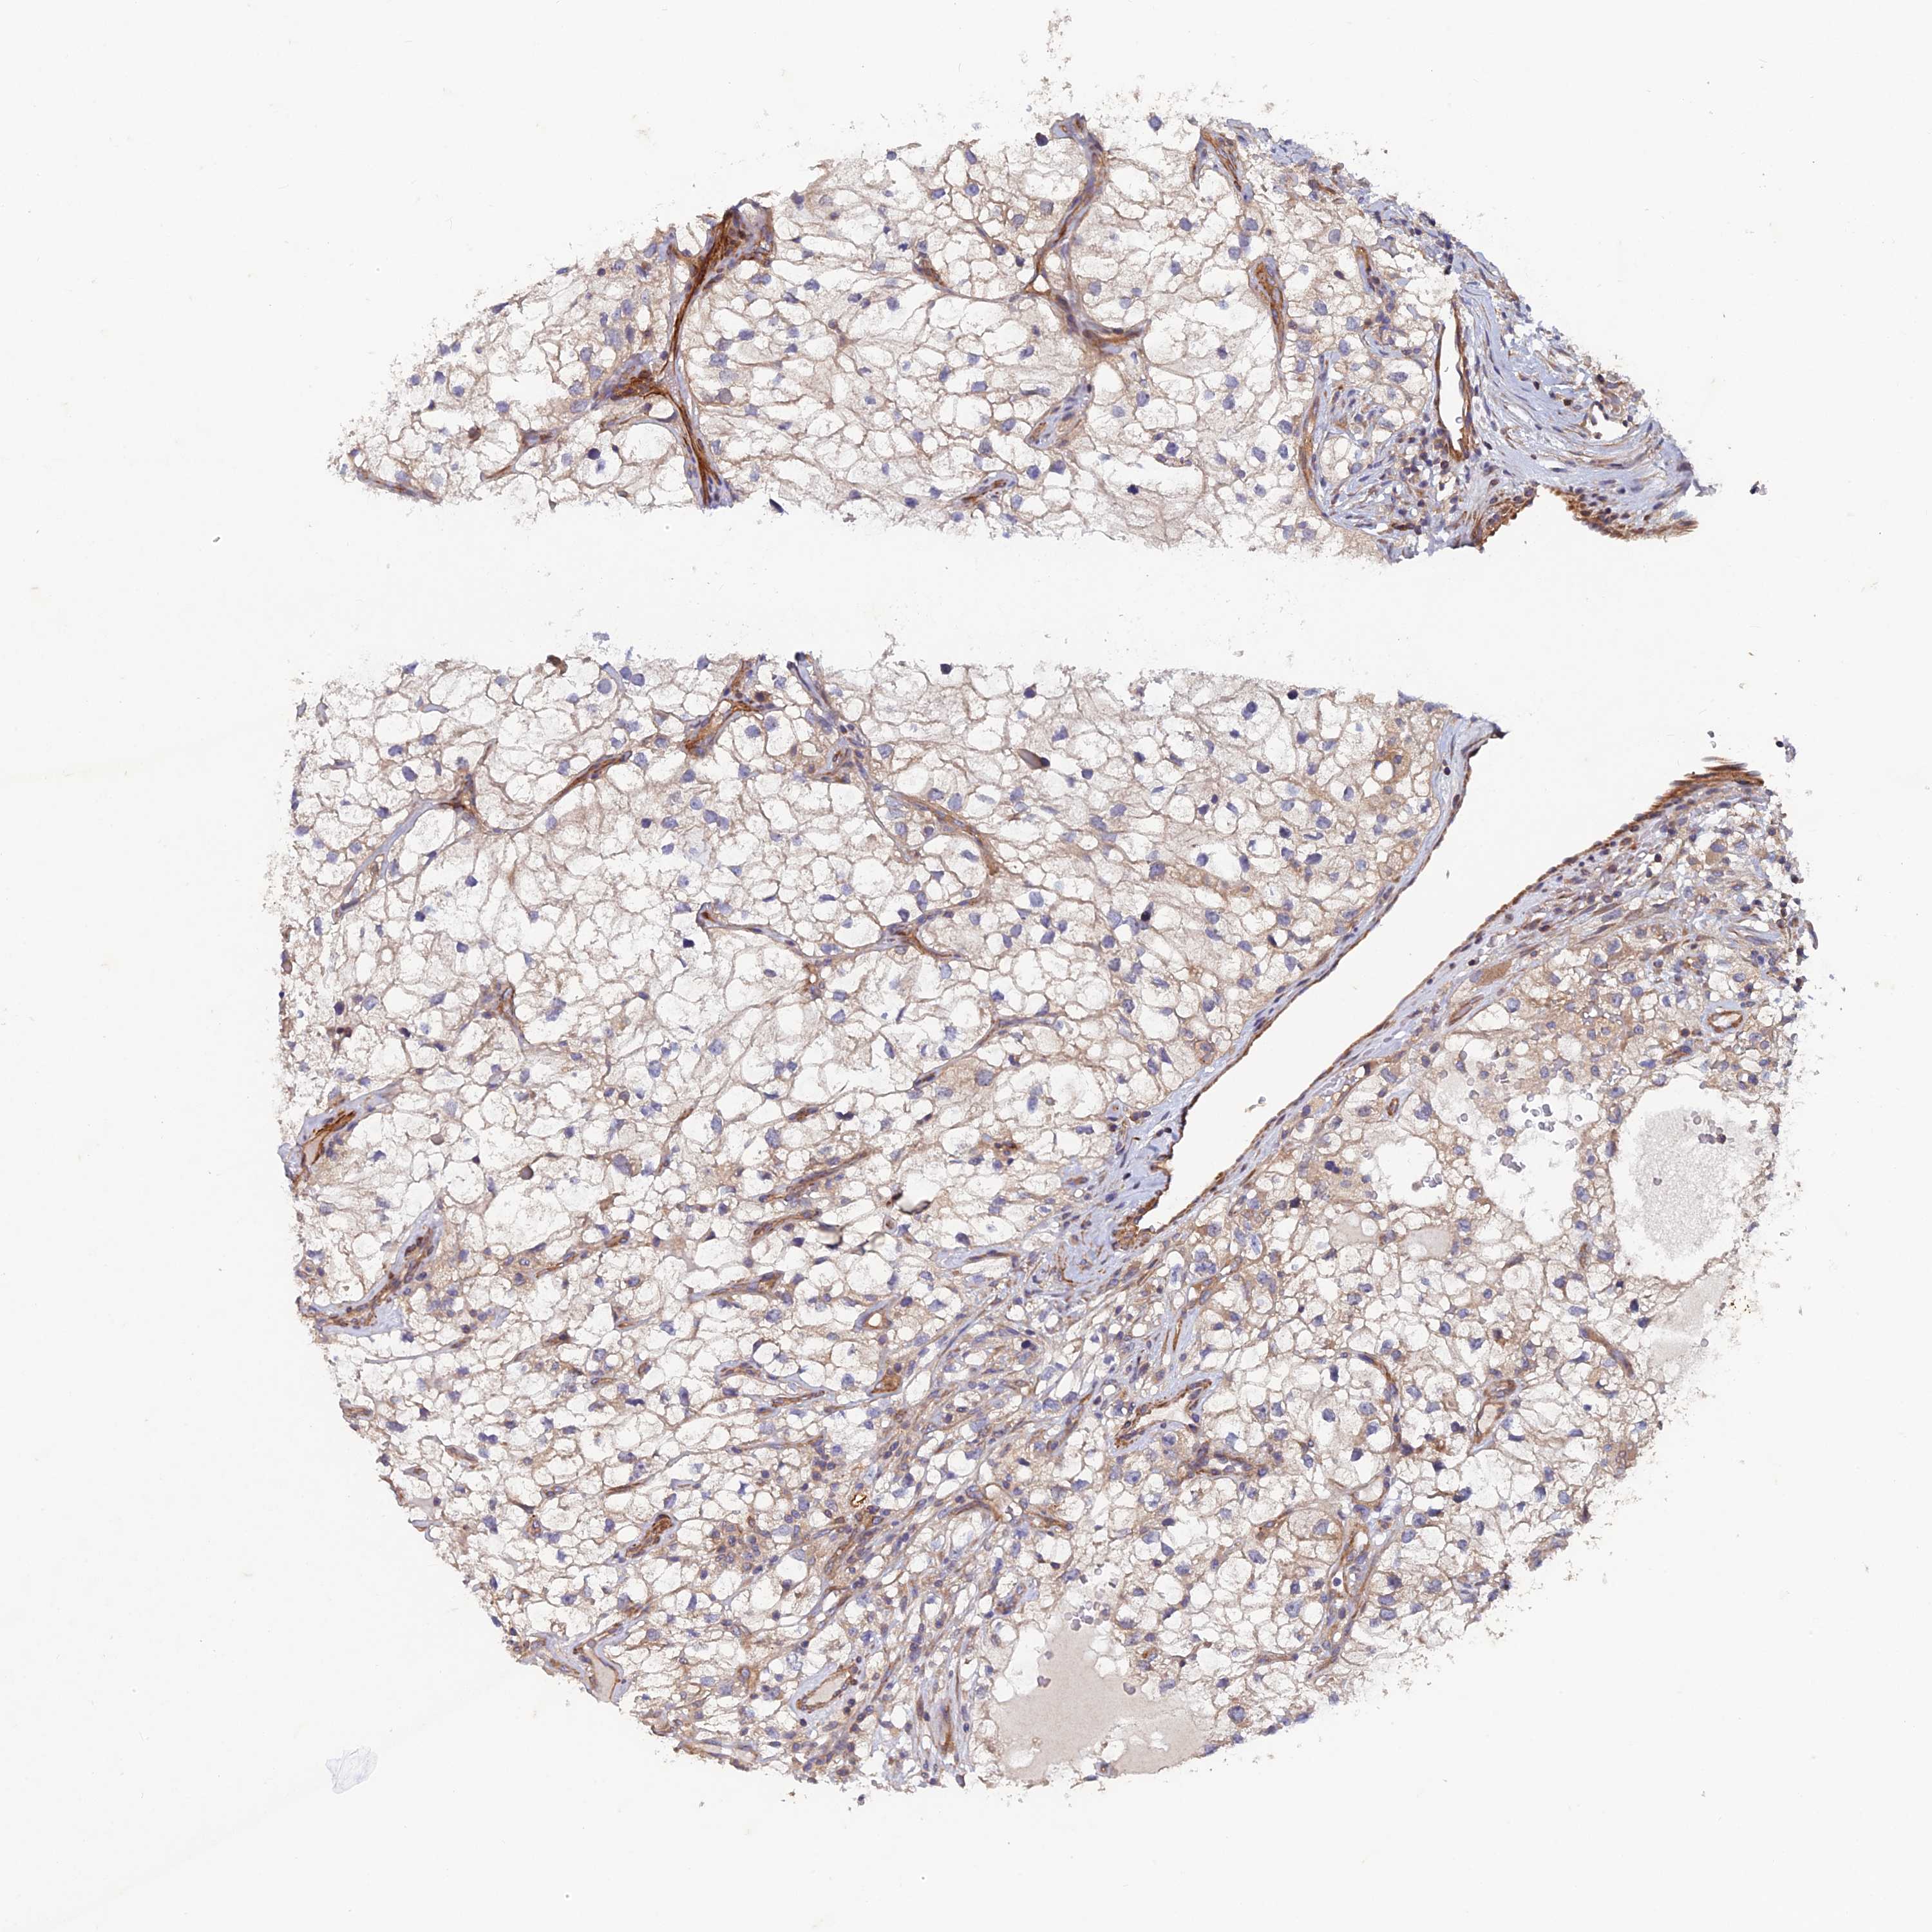

KIDNEY RENAL CLEAR CELL CARCINOMA (TCGA) - Interactive survival scatter ploti

The Survival Scatter plot shows the clinical status (i.e. dead or alive) for all individuals in the patient cohort, based on the same data that underlies the corresponding Kaplan-Meier plots. Patients that are alive at last time for follow-up are shown in blue and patients who have died during the study are shown in red.

The x-axis shows the expression levels (FPKM) of the investigated gene in the tumor tissue at the time of diagnosis. The y-axis shows the follow-up time after diagnosis (years). Both axes are complimented with kernel density curves demonstrating the data density over the axes. The top density plot shows the expression levels (FPKM) distribution among dead (red) and alive patients (blue). The right density plot shows the data density of the survived years of dead patients with high and low expression levels respectively, stratified using the cutoff indicated by the vertical dashed line through the Survival Scatter plot. This cutoff is automatically defined based on the FPKM cutoff that minimizes the p-score. The cutoff can be changed by dragging the vertical line or by entering a cutoff value in the square labeled "Current cut-off".

Under the Survival Scatter plot the p-score landscape (black curve; left axis) is shown together with dead median separation (red curve; right axis). Dead median separation is the difference in median mRNA expression between patients who have died with high and low expression, respectively. It is calculated as follows: median FPKM expression of dead patients with high expression - median FPKM expression of dead patients with low expression. This is intended to aid the user in visually exploring custom cutoffs and the associated p-scores and dead median separation.

Individual patient data is displayed and can be filtered by clicking on one or more of the category buttons on the top of the page. Categories describing expression level and patient information include: high, low, alive, dead, female, male and tumor stages. The scale of the x-axis can be toggled between linear and log-scale by clicking on the "x log" button. Mouse-over function shows TCGA ID, patient information and mRNA expression (FPKM) for each patient.

& Survival analysisi

Kaplan-Meier plots summarize results from analysis of correlation between mRNA expression level and patient survival. Patients were divided based on level of expression into one of the two groups "low" (under cut off) or "high" (over cut off). X-axis shows time for survival (years) and y-axis shows the probability of survival, where 1.0 corresponds to 100 percent.

NCAPG is potential prognostic, high expression is unfavorable in Kidney Renal Clear Cell Carcinoma (TCGA)

Best expression cut offi

Based on the FPKM value of each gene, patients were classified into two groups and association between prognosis (survival) and gene expression (FPKM) was examined. The best expression cut-off refers the FPKM value that yields maximal difference with regard to survival between the two groups at the lowest log-rank P-value. Best expression cut-off was selected based on survival analysis .

When clicking on this number, the vertical dashed line indicating cut-off, the interactive survival plot, and the Kaplan-Meier curve will be adjusted to show results based on the best expression cut-off.

: 2.05

TCGA RNA samplesi

RNA-seq data is reported as average FPKM (number Fragments Per Kilobase of exon per Million reads), generated by the The Cancer Genome Atlas (TCGA) .

Normal distribution across the dataset is visualized with box plots, shown as median and 25th and 75th percentiles. Points are displayed as outliers if they are above or below 1.5 times the interquartile range. FPKM values of the individual samples are presented next to the box plot.

Average pTPM 1.5

Number of samples 521